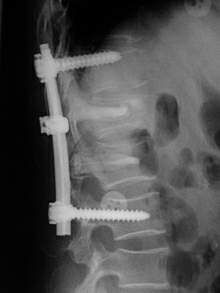

3.影像學檢查絕大多數病例可通過X線平片獲得確診。

短頸畸形2.屈伸拉動力性頸椎側位片,融合椎體節段失去正常頸椎的圓滑曲線,椎間隙不發生變化。

3.短頸畸形在X線正側位片上很難清楚地顯示畸形部位,表現有以下幾點特徵:

①頸椎兩個或兩個以上椎體和附屬檔案的部分或全部融合。

②一個或多個椎間隙消失或部分消失。

③椎體扁而寬,有時為半椎體畸形。

④融合椎體的鄰近頸椎節段增生、退變。椎管矢狀徑減小形成椎管狹窄。

⑤可合併其他畸形。